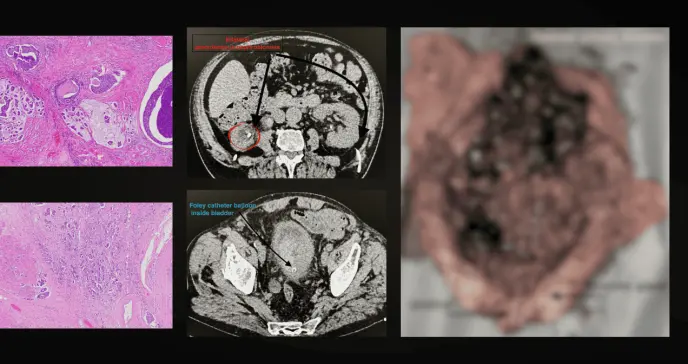

Los estudios iniciales revelaron anemia severa con hemoglobina en 4.8 g/dl, marcadores inflamatorios elevados y deterioro de la función renal. El urocultivo identificó Providencia alcalifaciens sensible a antibióticos, mientras que las imágenes mostraron una masa vesical de considerables dimensiones con signos de invasión local y necrosis.

La cistoscopia confirmó posteriormente la presencia de un tumor friable que ocupaba casi toda la vejiga.

El estudio anatomopatológico definitivo confirmó un carcinoma urotelial de alto grado con invasión de la capa muscular propia y presencia de angioinvasión. Tras la cirugía radical, el paciente experimentó una mejoría clínica notable en apenas 48 horas, con normalización progresiva de los parámetros inflamatorios y de la función renal. Fue dado de alta con ureterostomías cutáneas funcionantes y programado para seguimiento oncológico especializado.